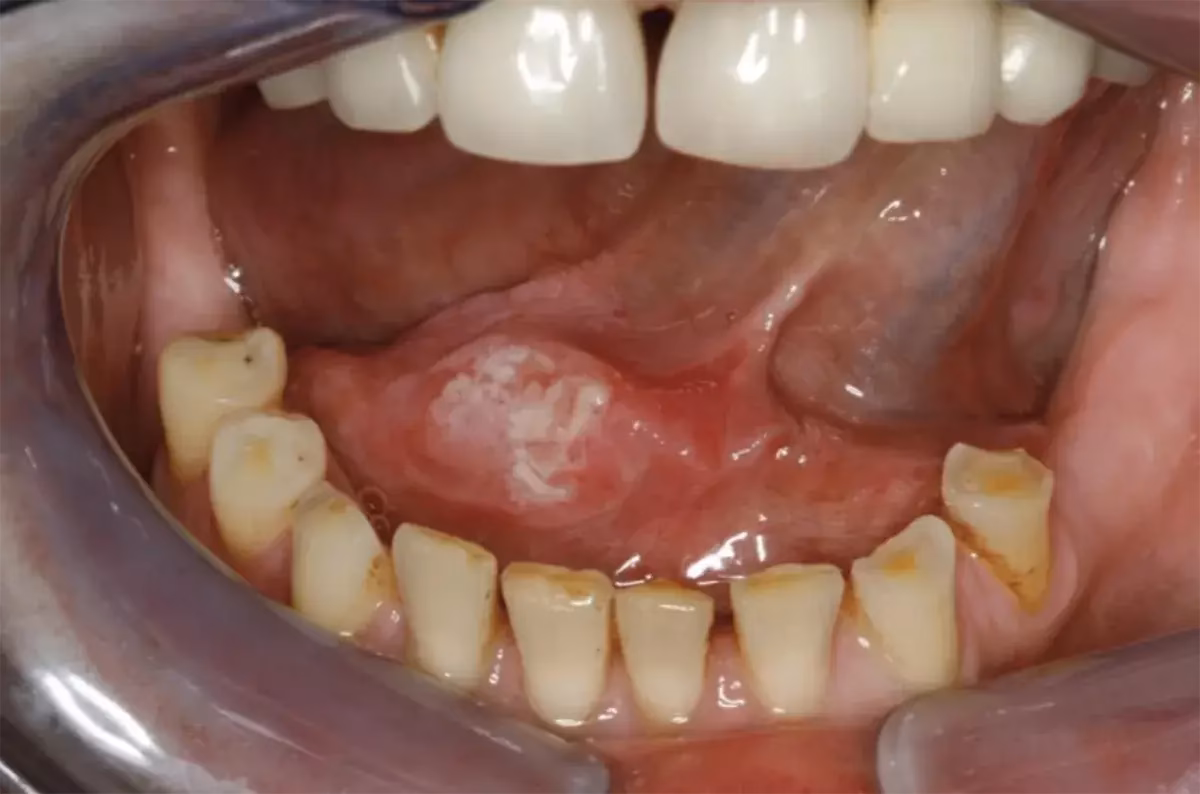

- Røde (erytroplaki) eller hvide (leukoplaki) pletter på tungen, som ikke kan skrabes af.

De tidligste tegn kan omfatte smerter i munden og en knude eller et sår på siden af tungen, der kan være smertefuldt, ikke heler og bløder let. Røde eller hvide pletter, der ikke forsvinder, er også et tidligt advarselstegn.